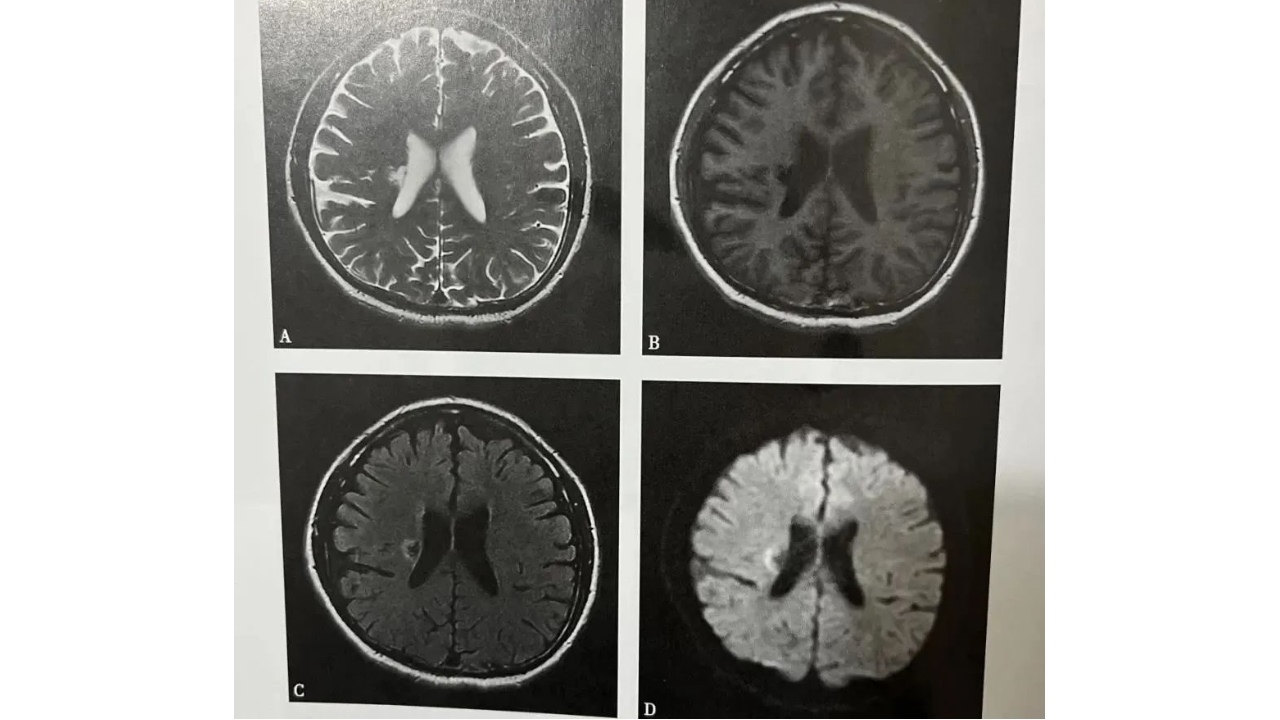

图1.图脑梗死(慢性期)

A~D(A.T2WI,B.T1WI,C.T2WI-FLAIR,D.DWI:右侧侧脑室体旁可见小片状长T1长T2信号灶,最大截面约12mmx10mm,边界尚清,FLAIR及DWI示病灶中心呈低信号灶,边缘呈稍高信号